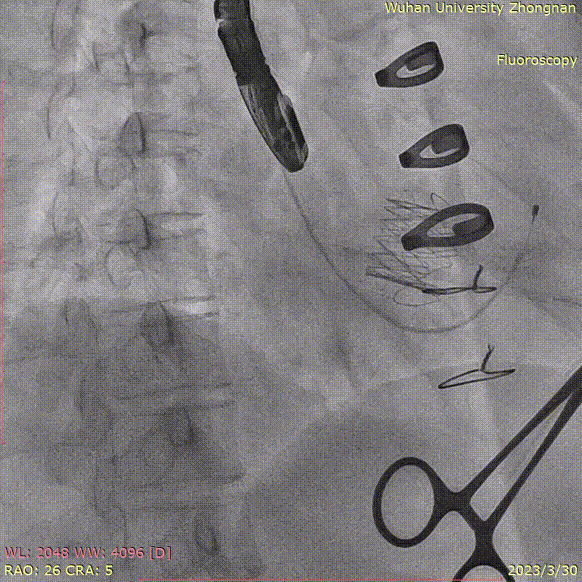

释放定位件,三个定位件均入瓣角,形态良好:

准备释放瓣膜:

释放瓣膜,先打开瓣膜鼻锥,形态位置满意后再让瓣膜完全释放:

原有生物瓣架提供支撑力,瓣膜得以持续膨胀,并获得良好形态: